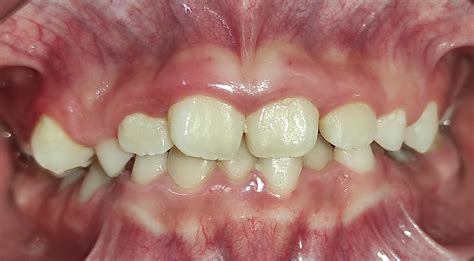

1. Dental

Este tipo de maloclusión ocurre cuando los dientes están desalineados pero los huesos maxilares tienen una relación normal entre ellos. Suele tratarse con ortodoncia y tener un buen pronóstico, ya que el problema no involucra la estructura ósea. Para una clase III que es únicamente dental, el tratamiento indicado es la ortodoncia, aunque es importante mencionar que una mordida cruzada funcional conservada en el tiempo puede transformarse en esqueletal, de ahí la importancia de un tratamiento precoz.